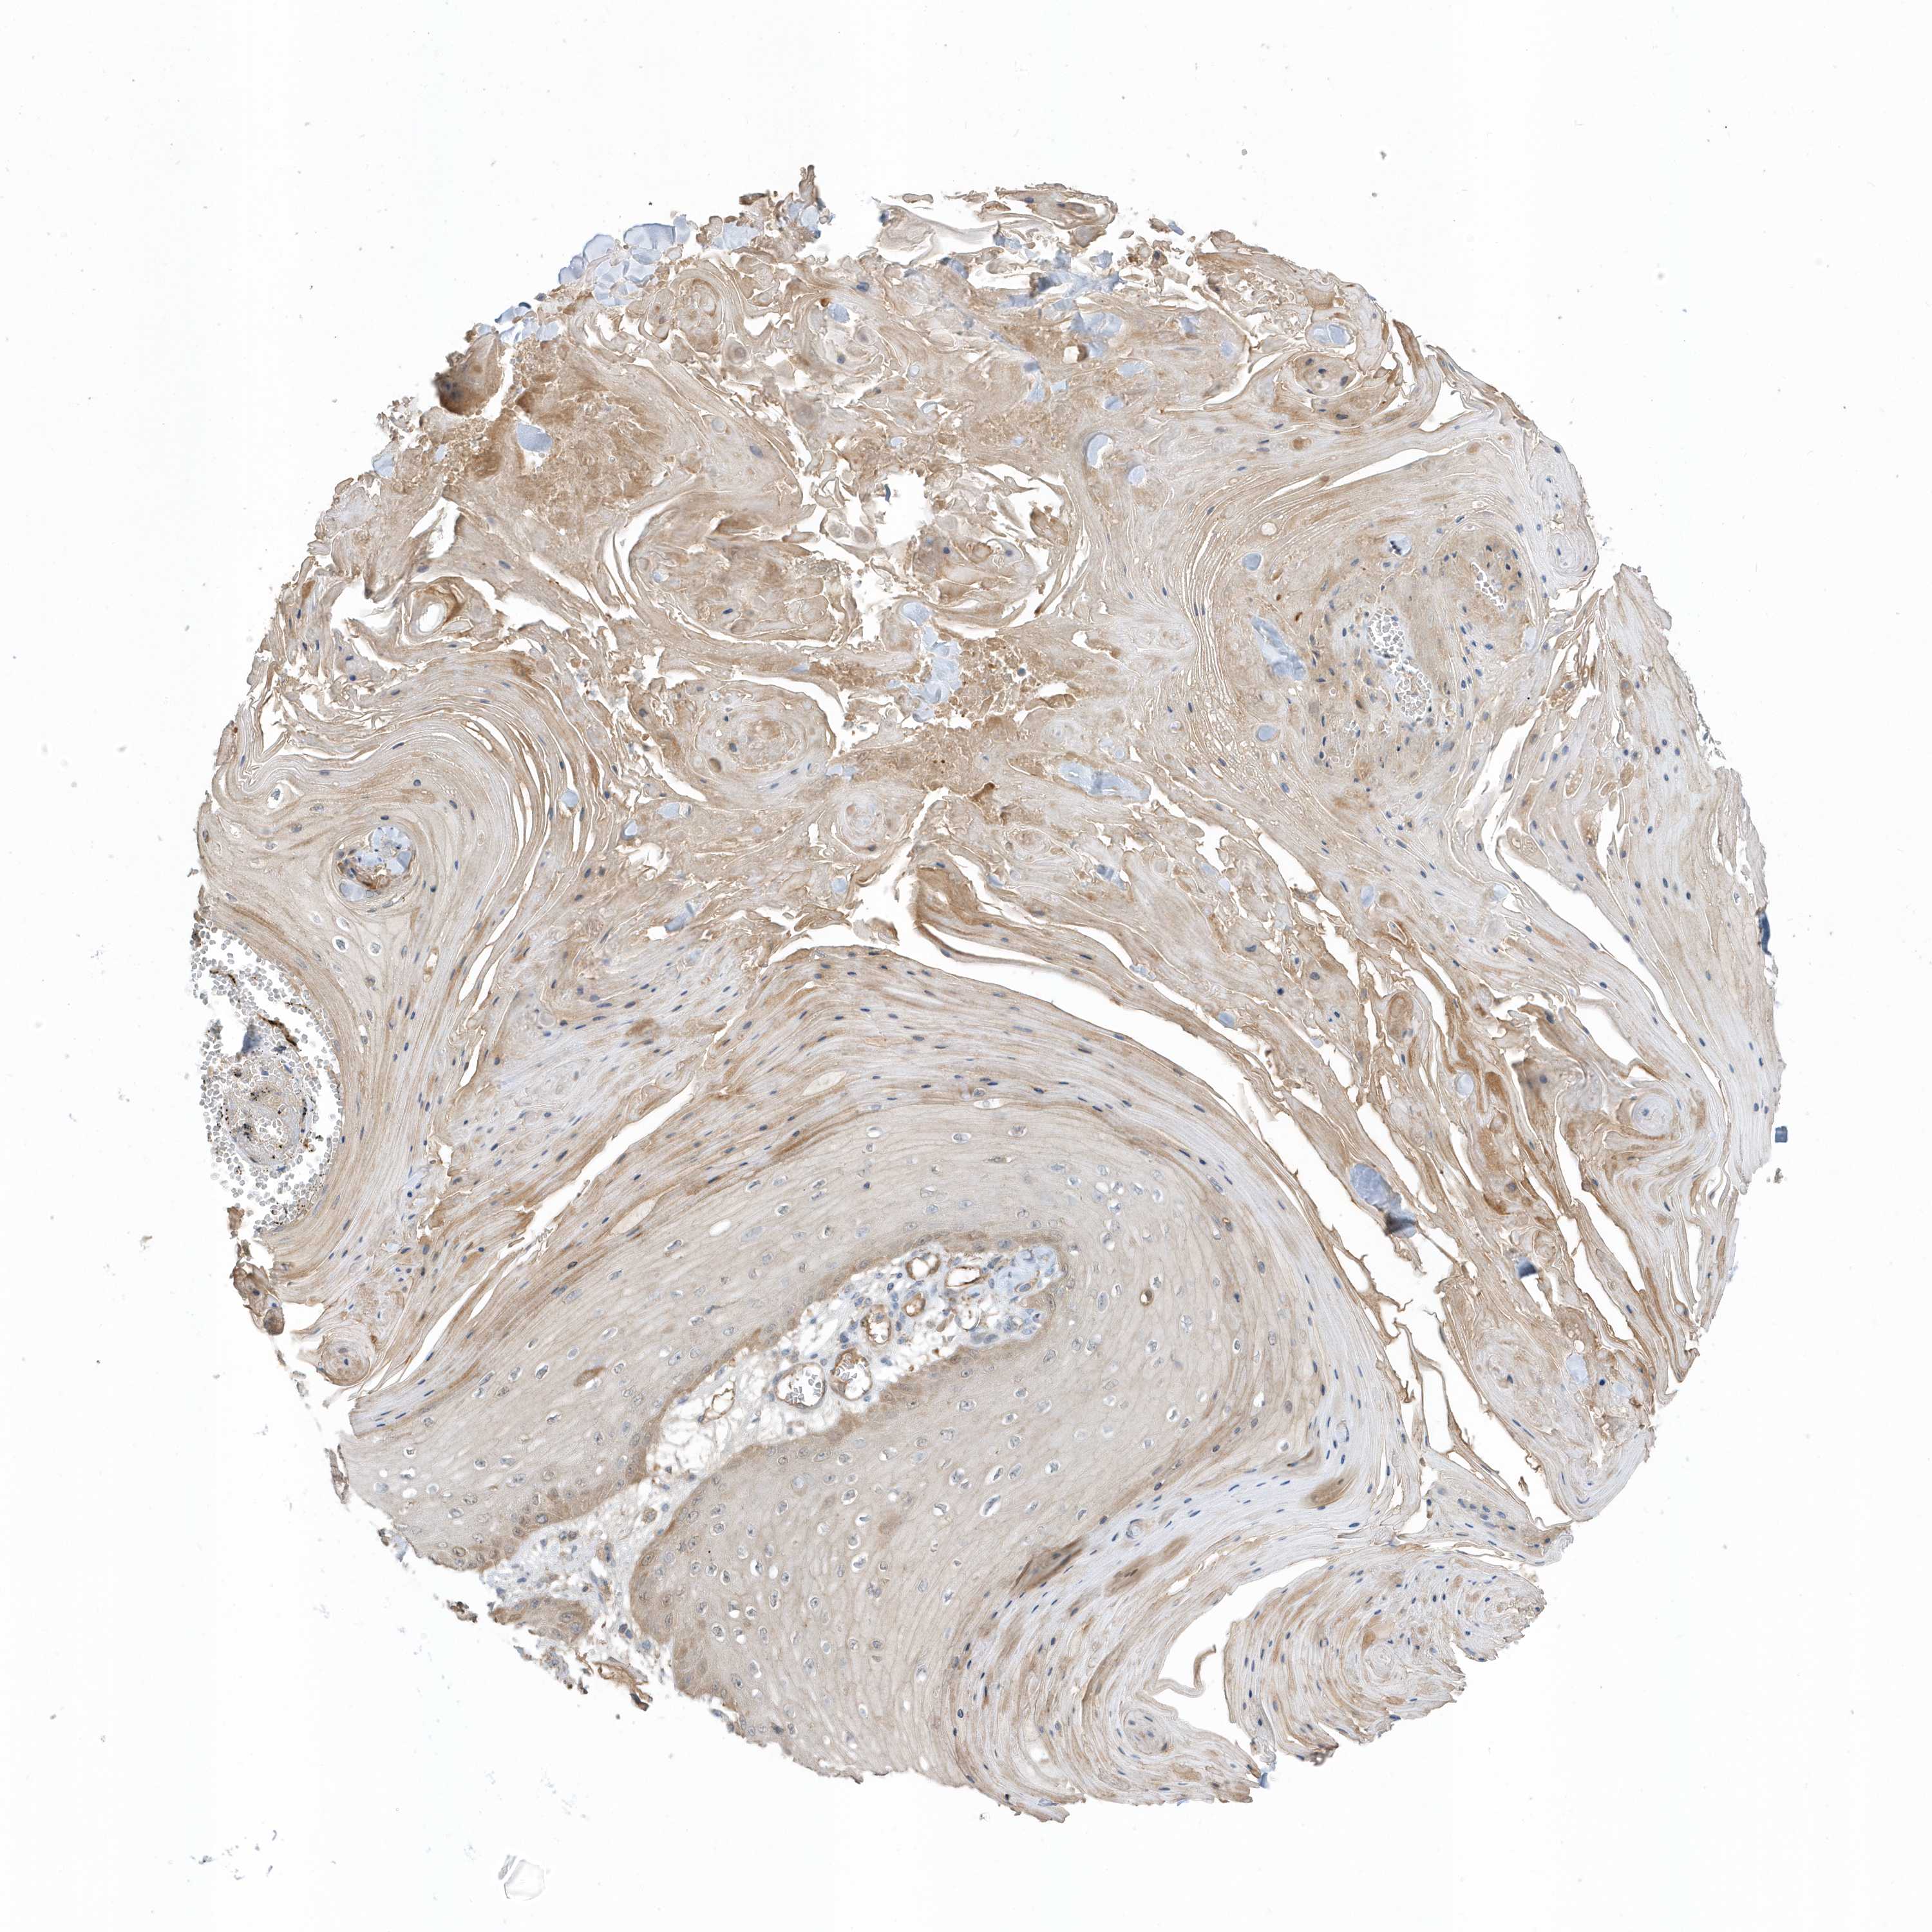

Basal cell and squamous cell cancer

SKIN CANCER - Protein expressioni

A mouse-over function shows sample information and annotation data. Click on an image to view it in a full screen mode. Samples can be filtered based on level of antibody staining by selecting one or several of the following categories: high, medium, low and not detected. The assay and annotation is described here.

Each image is clickable and will lead to virtual microscopy that enables deeper exploration of all samples and also displays staining intensity scores, fraction scores and subcellular localization as well as patient and tissue information for each sample.

Antibody HPA035844

Antibody HPA035845

Squamous cell carcinoma, metastatic, NOS